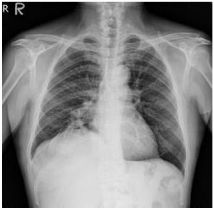

1. A 39-year-old man had this chest X-ray on his health exam. No any clinical symptoms.